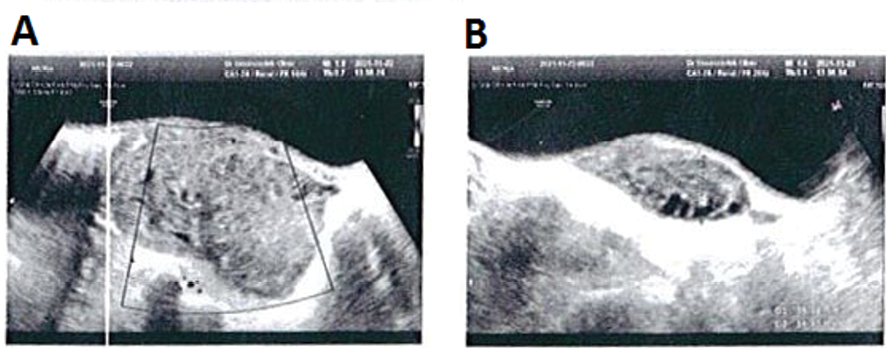

Ultrasound imaging of the abdomen and pelvis indicated an enlarged heterogeneous right ovary measuring 7.1cm × 4.2cm × 3cm, with no indication of vascular flow on color Doppler evaluations, reflecting an ovarian torsion diagnosis (Figure-1). Furthermore, the uterus was not visible in grayscale ultrasonic images due to the right ovary’s displacement from its typical location. The cul-de-sac exhibited a complete absence of free pelvic fluid. During an emergency laparotomy, the adnexa on the right side presented with torsion and discoloration, while the ovary on the left side exhibited normal characteristics (Figure-2). We detorted the adnexa but did not perform oophoropexy for it. Upon examining the right ovary’s perfusion, it was discovered to be intact with the fresh vascular flow but just a minor shift in the color of the adnexal tissue to pink.

The clinical presentation exhibits variability among individuals presenting with an acute surgical abdomen, the presence of a palpable tumor, and an increased leukocyte count [18–20]. It can be said that history, clinical symptoms, and imaging can play a crucial role in diagnosing OT. Ultrasound is a standard imaging technique to diagnose OT since it can evaluate ovarian architecture and perfusion rapidly and non-invasively [22]. Ultrasound detects adnexal torsion 92% sensitively and 96% specifically [23]. Ultrasonography has been identified as an effective method for detecting torsion, wherein the absence of Doppler artery flow and ovarian enlargement serves as typical characteristics [5, 24]. However, it is important to note that these features may not be consistently present [5, 24]. The preservation of Doppler arterial flow in cases of acute torsion is predominantly observed due to the initial alteration of venous and lymphatic flow. The exclusion of torsion in ovarian torsion (OT) cannot be definitively determined solely through the utilization of normal Doppler results [5, 25]. Ultrasound findings indicative of OT include enlarged ovaries, peripheral follicle distribution, aberrant adnexal position, and free fluid [23, 25, 26]. Furthermore, a coiled or twisted vascular pedicle detected on ultrasonography (known as whirlpool signs) indicates torsion [27, 28]. Although ultrasound might be helpful, a clinical evaluation is still necessary to diagnose OT. In this particular case, the ultrasound examination revealed an abnormality characterized by an increased size of the right ovary and diminished blood flow as detected by Doppler imaging. This finding, in the context of the patient's presenting symptom of abdominal pain, prompted a diagnosis of right ovarian torsion prior to surgical intervention.

Figure 1. Ultrasound image of an 8-year-old girl with right ovarian torsion.